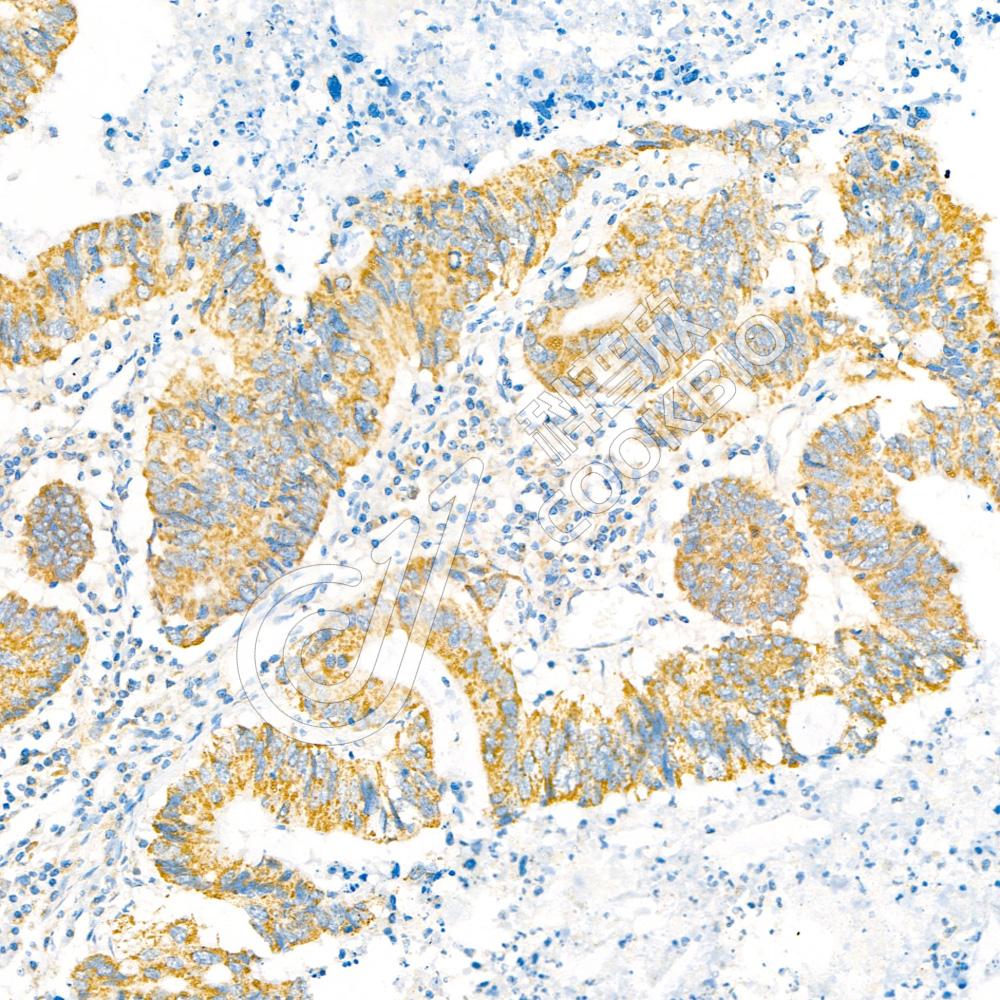

IHC检测GSK3 beta蛋白(货号 K133297).

样品: 大鼠睾丸, 4%多聚甲醛 (货号KSG1101) 固定12-24小时.

抗原修复: 柠檬酸抗原修复液(干粉, pH 6.0) (KSG1201), 98℃, 20分钟.

—抗: 1: 600稀释, 4℃ 孵育过夜.

二抗: S-vision免疫组化多聚二抗(山羊抗兔),即用型 (货号KB3906), 室温孵育20分钟.